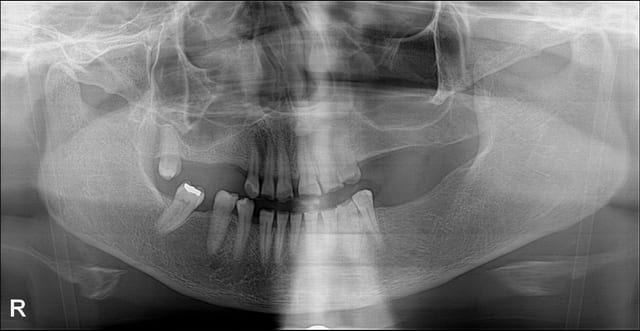

Je compte d'abord poser les implants en posterieur pour remonter la DV.

Sur les anterieures, est il possible de faire des facettes ou bien est ce couronne obligatoirement?

Pour les centrales maxillaire, il faudra faire une elongation coronaire de 21. Je en pense pas qu'on puisse allonger beaucoup 11 et 21 car il semble qu'il y ait eu egression compensatrice.

Si je fais des facettes, ce sera une preparation "butt joint" je pense car il faudra une insertion vestibulaire vu que les dents sont fluocalciques.

Un détail (important) m'interpelle: comment comptes tu ménager suffisamment de place en postérieur pour restaurer un calage? Et comment quantifies tu la perte de DV (si tant est qu'il y en ait)?

L'espace prothetique existe deja en posterieur a l'etat initial.

J'augmente la dv en posterieur de 2 mm environ c'est tout. Ca me permettra d'avoir la place pour faire couronnes ou facettes sur les incisives / canines mandibulaires.

Concernant le haut, sur les photos suivantes on voit bien que les bords libres sont situes a une hauteur a peu pres correcte.

Il faudra donc gagner de la hauteur en rognant sur le parodonte.